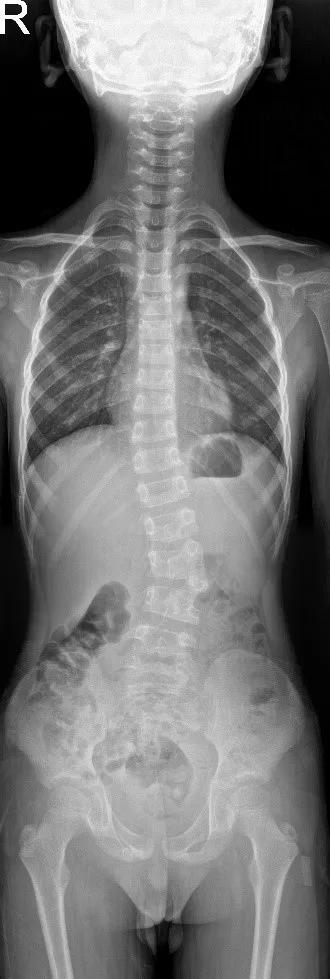

术前正位

术前侧位